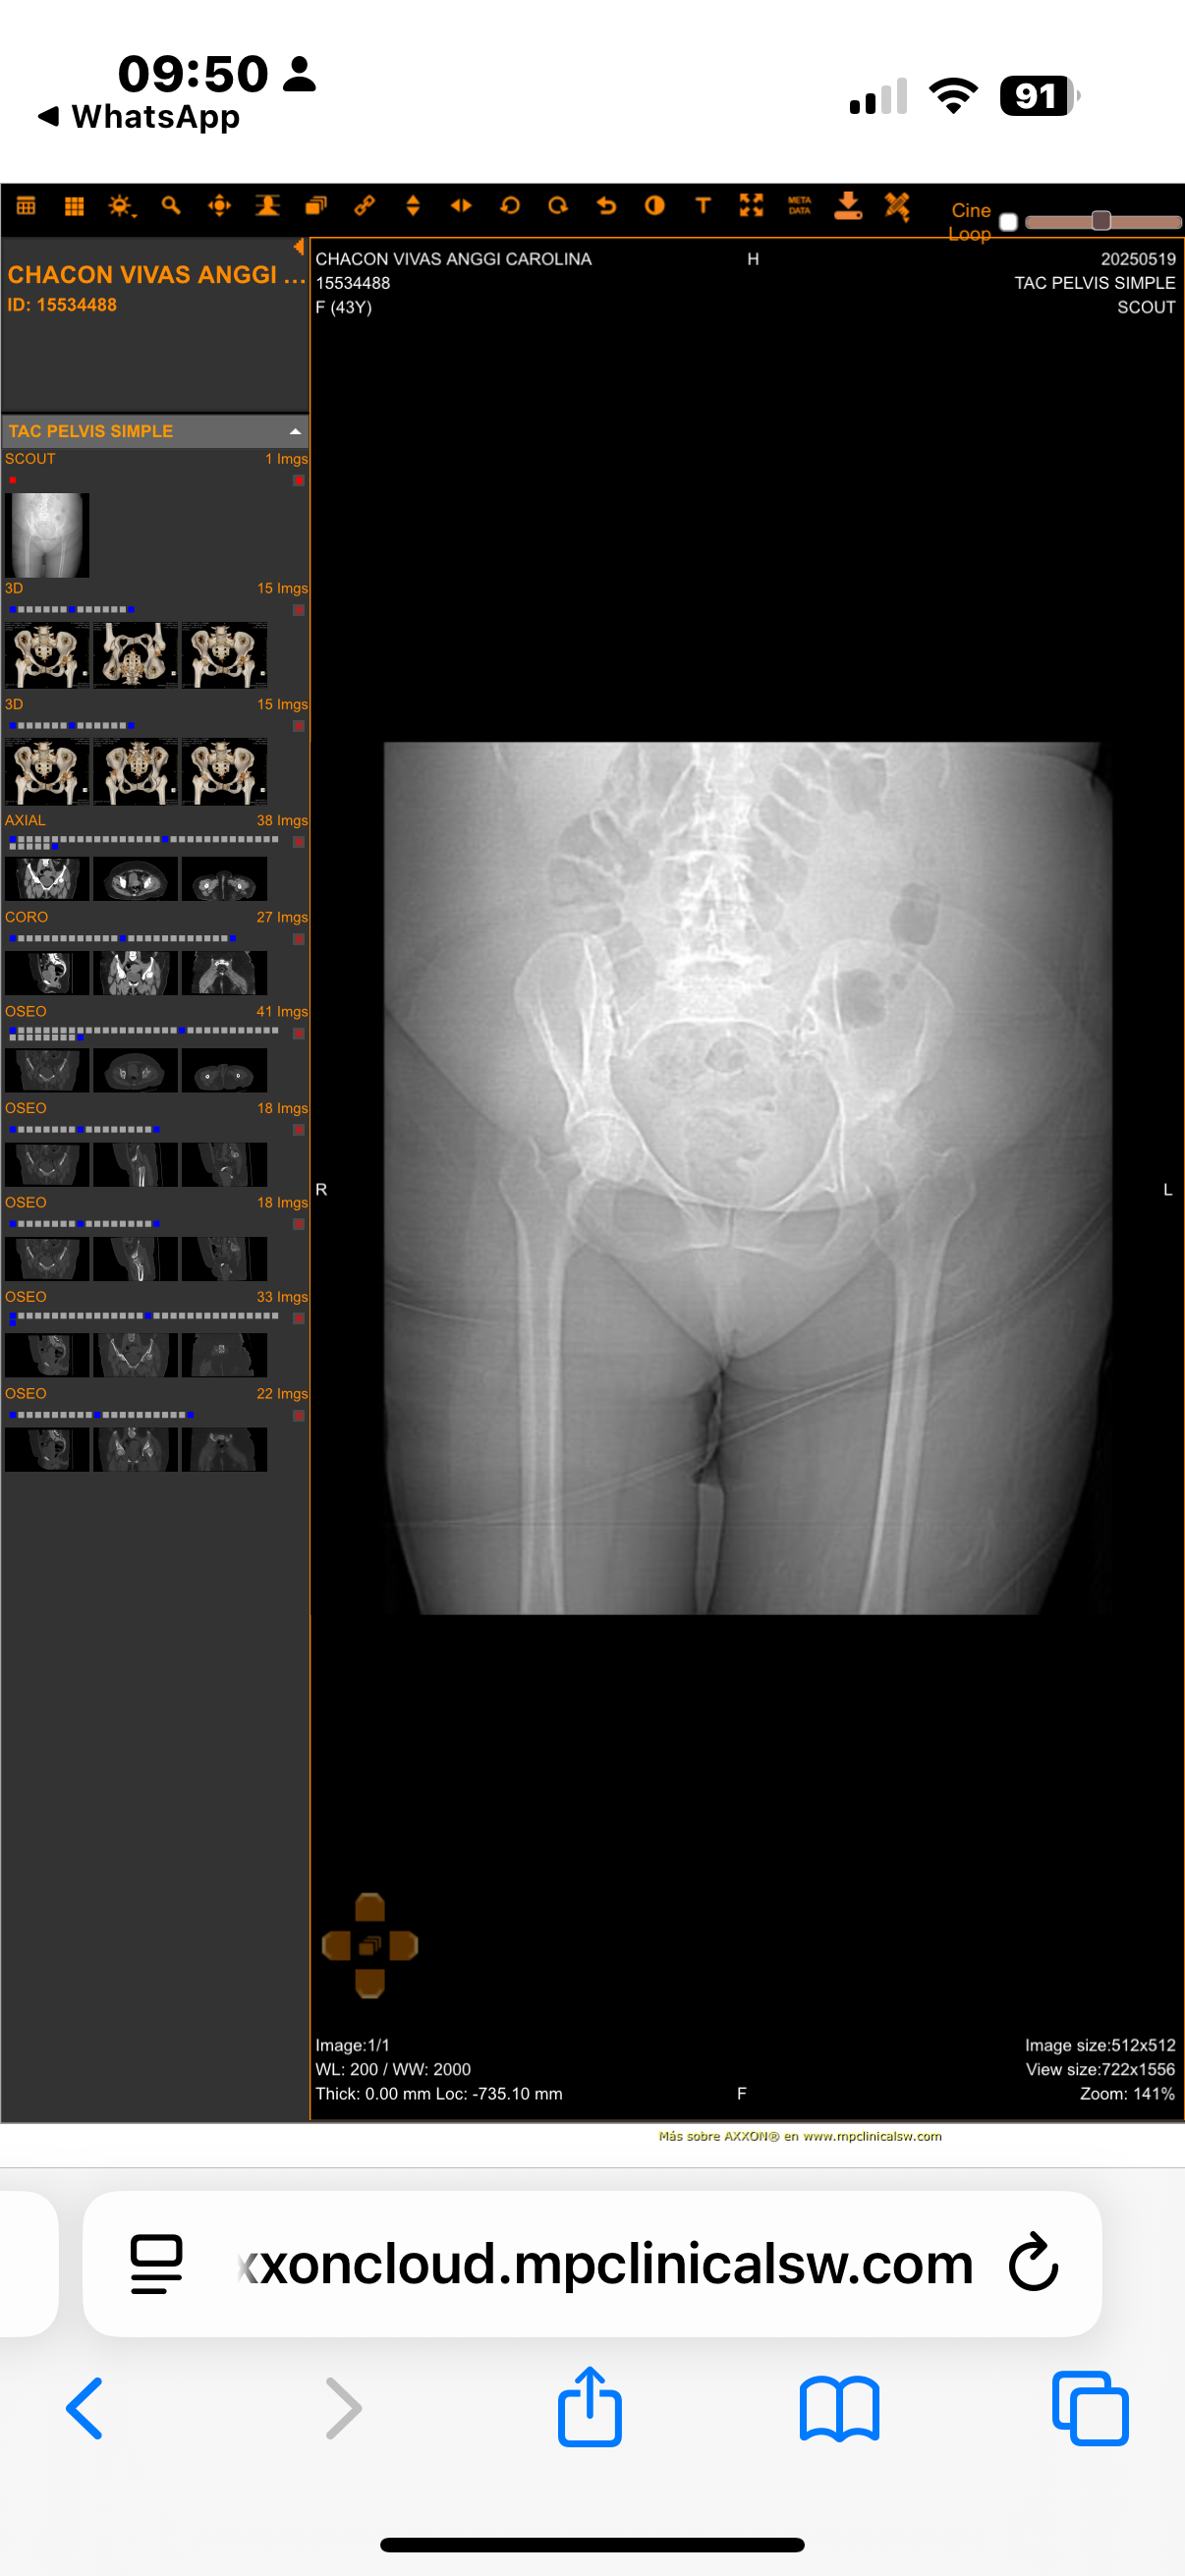

Para quienes deseen ver el informe médico con imágenes, pueden acceder al siguiente enlace:

Este es un visor médico seguro donde se puede observar el daño en la cadera que ha sido evaluado por los especialistas.

For those who wish to see the medical report with images, you can access it through the following link:

This is a secure medical viewer where you can see the damage to the hip as evaluated by specialists.